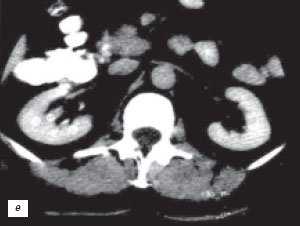

2. КТ при дефекте соединения паренхимы почки:

• Жиросодержащие углубления на передневерхней (реже - на задненижней) поверхности почек, которые иногда распространяются на почечный синус

(Справа) КТ, коронарная проекция: у этого же пациента лучше визуализированы жировые углубления и дефект верхнего полюса.